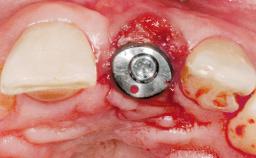

A 42-year-old female patient was referred to our clinic at the School of Dentistry of the University of São Paulo in November 2004, presenting a deficient restoration in the upper left central incisor. The clinical examination revealed no gingival retraction or any signs of gingival inflammation and, therefore, previous periodontal treatment was not considered. The patient presented a high lip line at full smile and a thin tissue biotype. This combination characterized a high-risk situation from an anatomic point of view, which required careful preoperative planning and cautious surgical execution.

Placement Protocol Immediate implant placement

Tooth Site Maxillary incisor or canine

Socket Morphology Single-root socket

Socket Integrity Sufficient, with intact bone walls

Bone Volume Sufficient, with intact walls

Type of Implants One-Piece